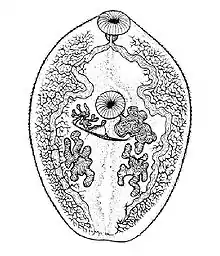

| An adult specimen stained with carmine | |

In size, shape, and color, Paragonimus westermani resembles a coffee bean when alive. Adult worms are 7.5 mm to 12 mm long and 4 mm to 6 mm wide. The thickness ranges from 3.5 mm to 5 mm. The skin of the worm (tegument) is thickly covered with scalelike spines. The oral and ventral suckers are similar in size, with the latter placed slightly pre-equatorially. The excretory bladder extends from the posterior end to the pharynx. The lobed testes are adjacent from each other located at the posterior end, and the lobed ovaries are off-centered near the center of the worm (slightly postacetabular). The uterus is located in a tight coil to the right of the acetabulum, which is connected to the vas deferens. The vitelline glands, which produce the yolk for the eggs, are widespread in the lateral field from the pharynx to the posterior end. Inspection of the tegumental spines and shape of the metacercariae may distinguish between the 30-odd species of Paragonimus spp. but the distinction is sufficiently difficult to justify suspicion that many of the described species are synonyms.[5]

- Adults: Adult flukes are typically reddish-brown and ovoid, measuring 7 to 16 mm by 4 to 8 mm, similar in size and appearance to a coffee bean. They are hermaphroditic, with a lobed ovary located anterior to two branching testes. Like all members of the Trematoda, they possess oral and ventral suckers.